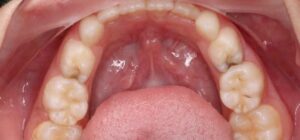

SSC (Stainless Steel Crown) là mão răng bằng thép không gỉ, được thiết kế sẵn với nhiều kích cỡ khác nhau, thường dùng để phục hồi răng sữa đã bị sâu lớn hoặc tổn thương nặng. Đây là một dạng phục hình toàn phần bao phủ toàn bộ thân răng, giúp bảo tồn và duy trì chức năng của răng sữa cho đến khi thay răng vĩnh viễn.